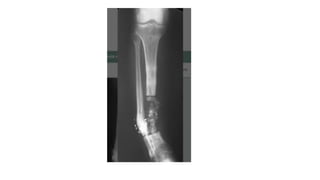

GAP NON UNION

• Gap nonunion presents a major challenge to the orthopedic surgeon,

• Open fractures with bone loss are most common in the tibia due to

its subcutaneous anatomical site, and a number of patients have